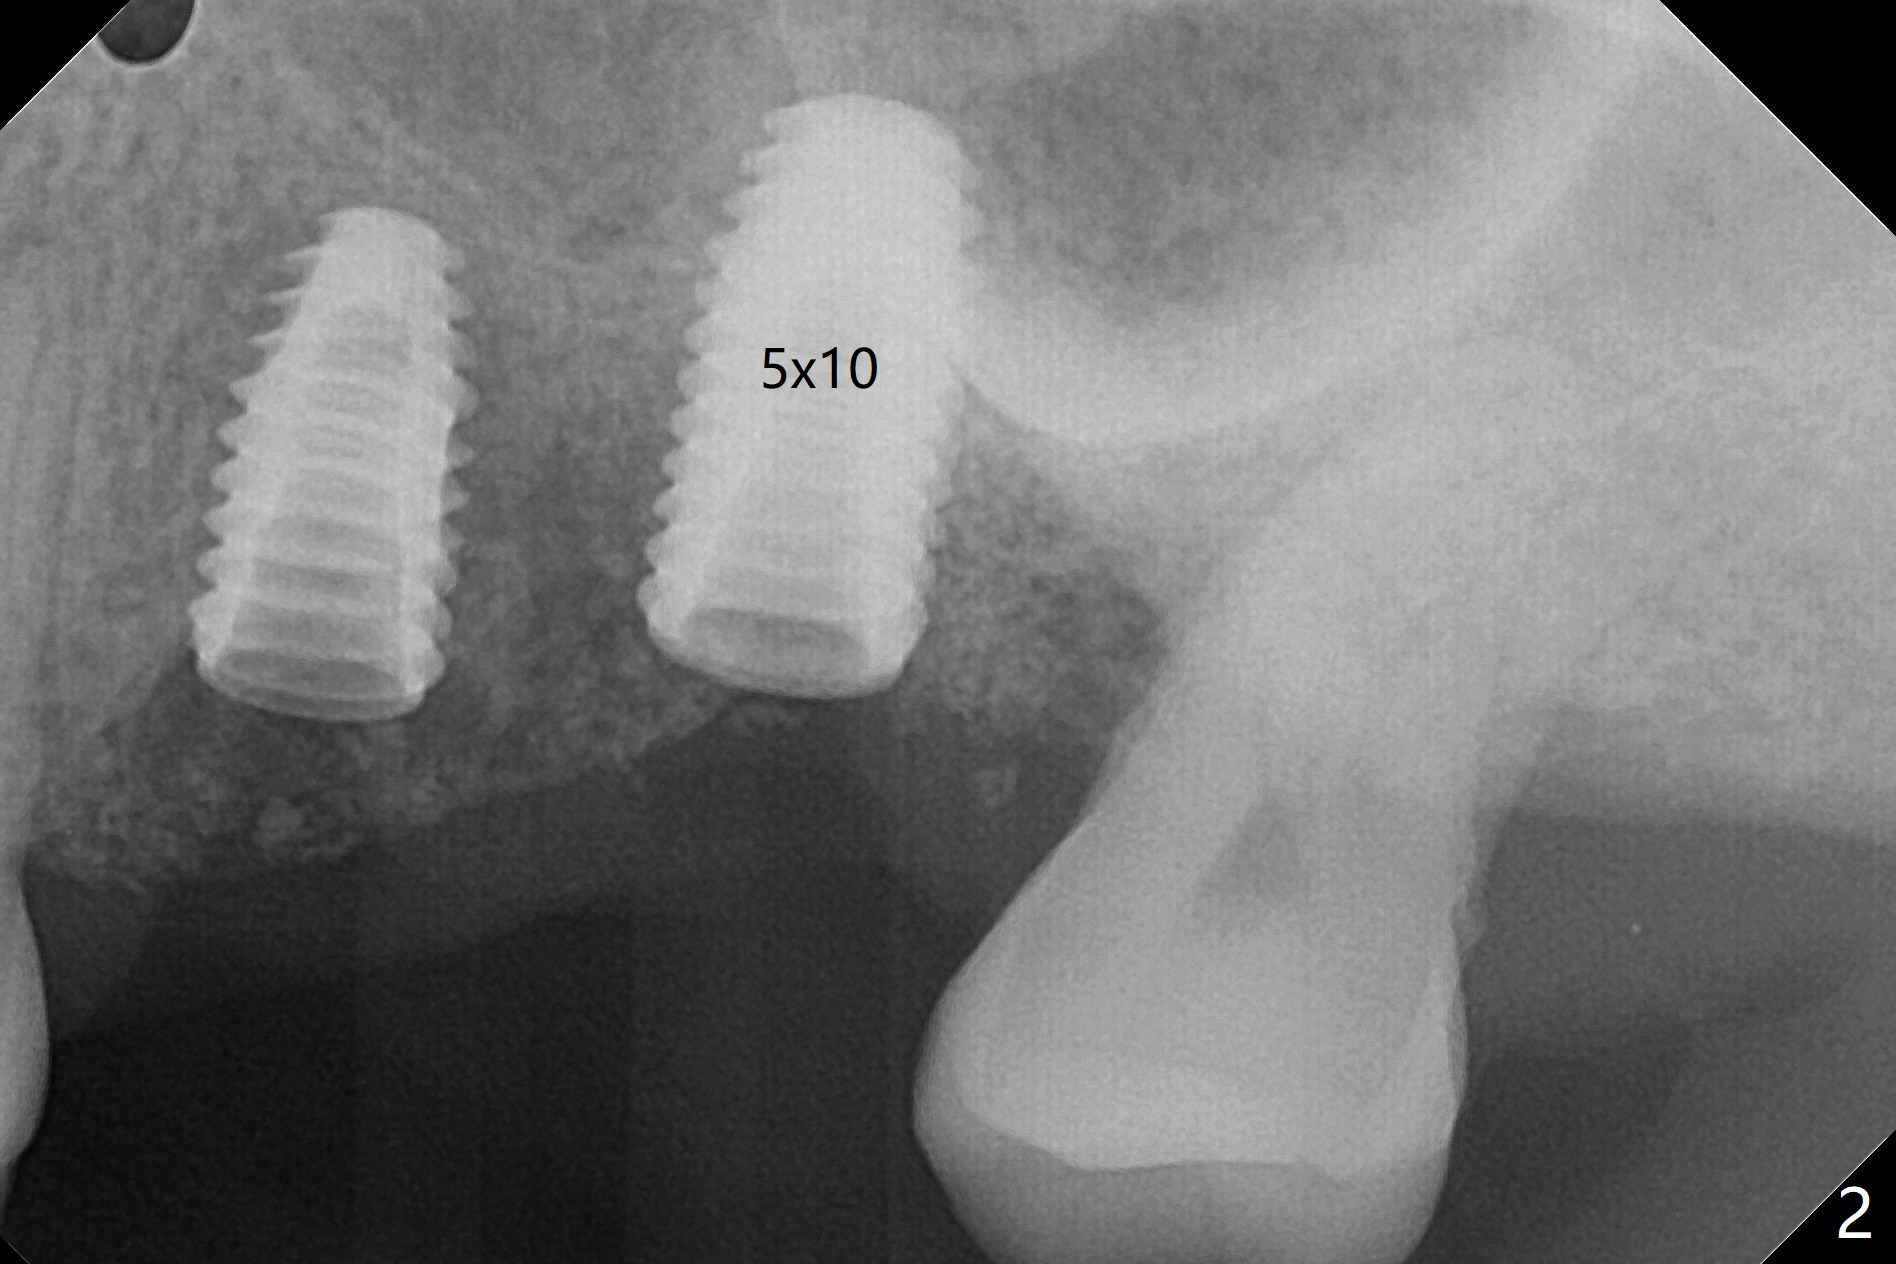

Fixture mount does not fit at #13 as an anchor. After 3.5x7.3 mm drill with 10.5 mm offset at #14, sinus lift drills (3.6x18 and 19 mm) are used. The sinus floor is intact. A 9 mm offset should be used. Following 4.0x10 mm dummy implant is placed for ~ 8.5 mm, the sinus floor is perforated while the sinus membrane is intact. After water lift, PRF membrane and allograft are inserted and pushed upward with the 4.0x10 mm dummy implant for ~ 10 mm (Fig.1). One more piece of PRF membrane and bone graft are lifted with a 4.5x10 mm dummy implant. A small dose of bone graft is elevated with a definitive implant (Fig.2,3, 5x10 mm). Is there enough bone to cover the apical part of the implant when the latter heals? When the patient returns for restoration 4.5 months postop, local oral hygiene is not good with light gingival erythema. There is tenderness when the healing abutment is being removed. It appears that osteointegraton is to occur; the mesial bone density is low (Fig.4 *). Healing abutment should be not placed when sinus lift repeatedly fails. In fact the implant is removed with the healing abutment 6.5 months postop. The buccal plate is missing, while the sinus floor is intact. Ossogen is placed, covered by Osteogen plug and sutured with PGA (Fig.5). The buccal plate remains concave 8 days postop (Fig.6 B). In the 4th trial, incision will be made, flaps dissected extensively with suture fixation. The existing guide is used to start osteotomy with point drill, followed by bone expansion. Reload the guide to place a narrower implant 4 or 4.5 mm with cover screw, and place sticky bone buccal. The latter is covered with PRF and suture. If stability is insufficient, perforate the sinus floor. Place a cemented abutment at #13 to hold periodontal dressing. Use profile drill if needed.Return to Upper Molar Immediate Implant, Trajectory II Xin Wei, DDS, PhD, MS 1st edition 08/13/2019, last revision 02/13/2021